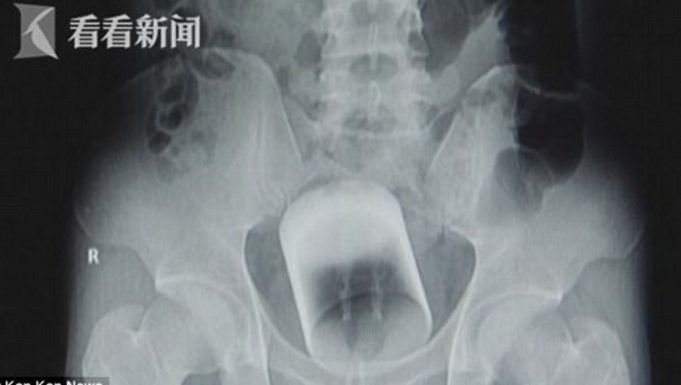

GUANGZHOU.- Un sujeto llegó al hospital de la Universidad Sun Yat Sen en Guangzhou, al sur de China, a las 2:00 horas del 31 de agosto, con un vaso de vidrio de siete centímetros de diámetro en el ano.

El...